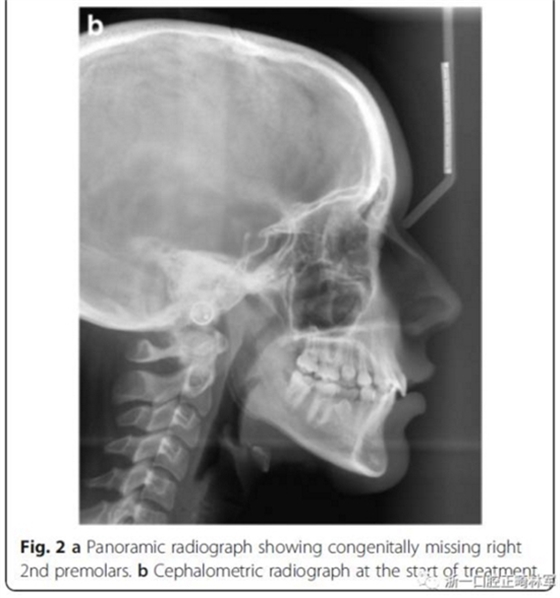

頭側(cè)分析,骨性I類關(guān)系,高角型